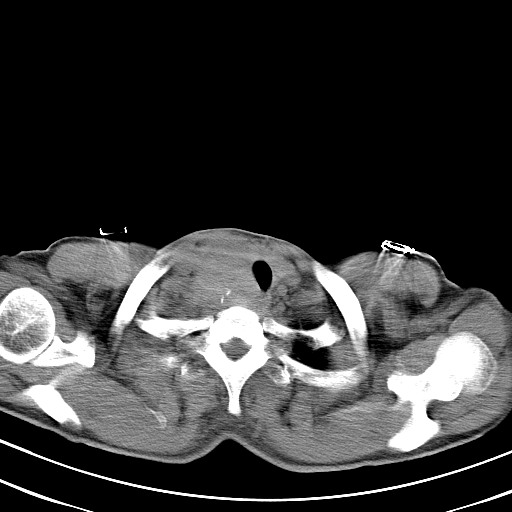

以下是引用汪涛同志在2007-8-2 0:40:00的发言:[br]病变虽然广泛,同时侵及双侧纵隔,但是无论左侧和右侧上下观察都是与右侧颈部甲状腺相延续的,而且强化幅度基本一致,又同时具有恶性病变病变的某些特征:肿块过大且密度不均,部分层面与正常纵隔结构分界不清,结合病史已有两年,考虑:胸内甲状腺肿恶变可能。[br]